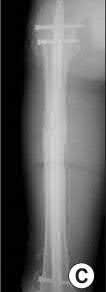

A 64-year-old woman is thrown off a horse, sustaining the injury shown in Figures A and B. She undergoes surgical fixation as seen in Figures C through E. What is the most commonly reported complication of this procedure?

The patient in the scenario has a 2-part proximal humerus fracture treated with a locking plate as seen in Figures A-E. The most common complication with the use of this implant is screw penetration. The terms screw cut out and penetration are often used interchangeably in the literature with cut out appearing more frequently in reports regarding intertrochanteric fractures.

Owsley et al retrospectively reviewed 53 proximal humerus fractures treated with locking plates and the same post-operative protocol. The most common complication was screw cut out or penetration, followed by varus displacement. They concluded that 3 and 4-part fractures in patients over 60 years have a higher incidence of failure.

Agudelo et al retrospectively reviewed 153 patients at a level-one trauma center treated with proximal humerus locking plates, investigating modes of failure for the implant. They determined that varus malreduction (head-shaft angle